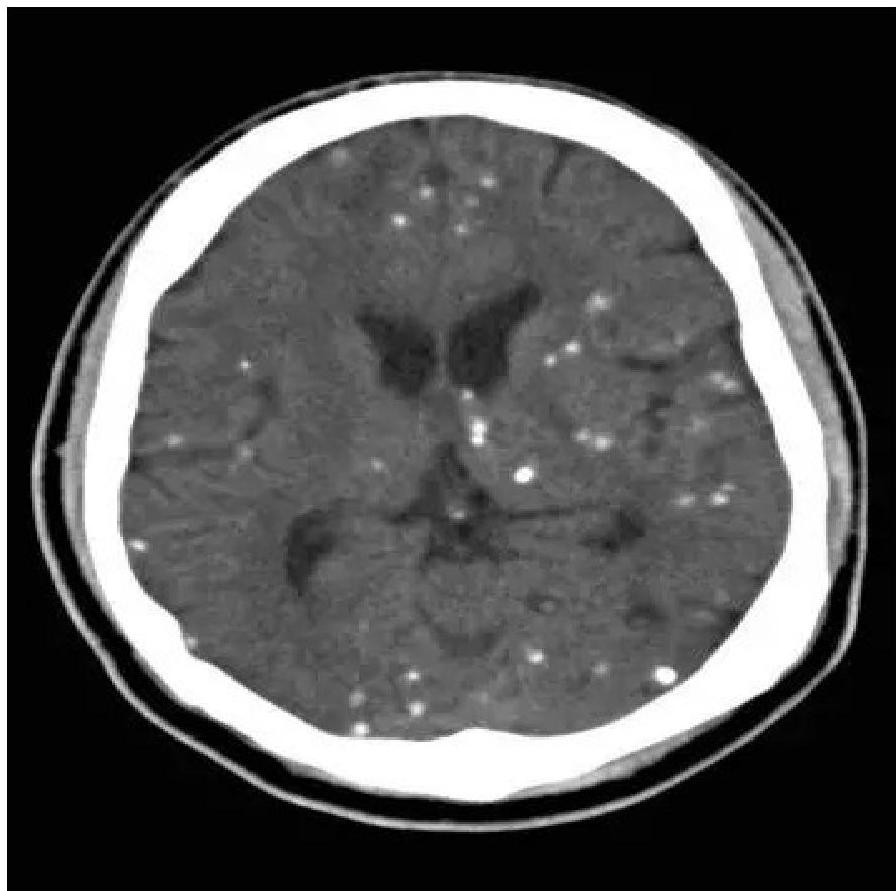

- Neurological: Microcephaly, Seizures, Intracranial calcifications (classically periventricular).

Ventriculomegaly and calcification of congenital CMV

- Imaging: Cranial ultrasound/CT → periventricular calcifications, ventriculomegaly.

- Intracranial calcification (diffuse, not periventricular like CMV).